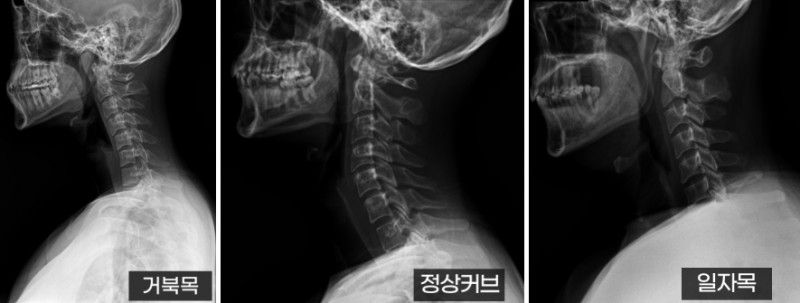

부산 거북목 일자목 우려의 만성 목통증 푸는 쉬운 운동과 치료!

부산거북목 이나 부산일자목 은 주로 경장근(목 앞쪽 깊은 곳에 있는 근육)의 약화와 목 뒤쪽 근육의 과도한 긴장으로 발생합니다.

정상적인 목 자세는 앞뒤 근육이 균형을 이루어야 하는데, 이 균형이 깨지면 뒷목이 뻣뻣해지는 것이죠.